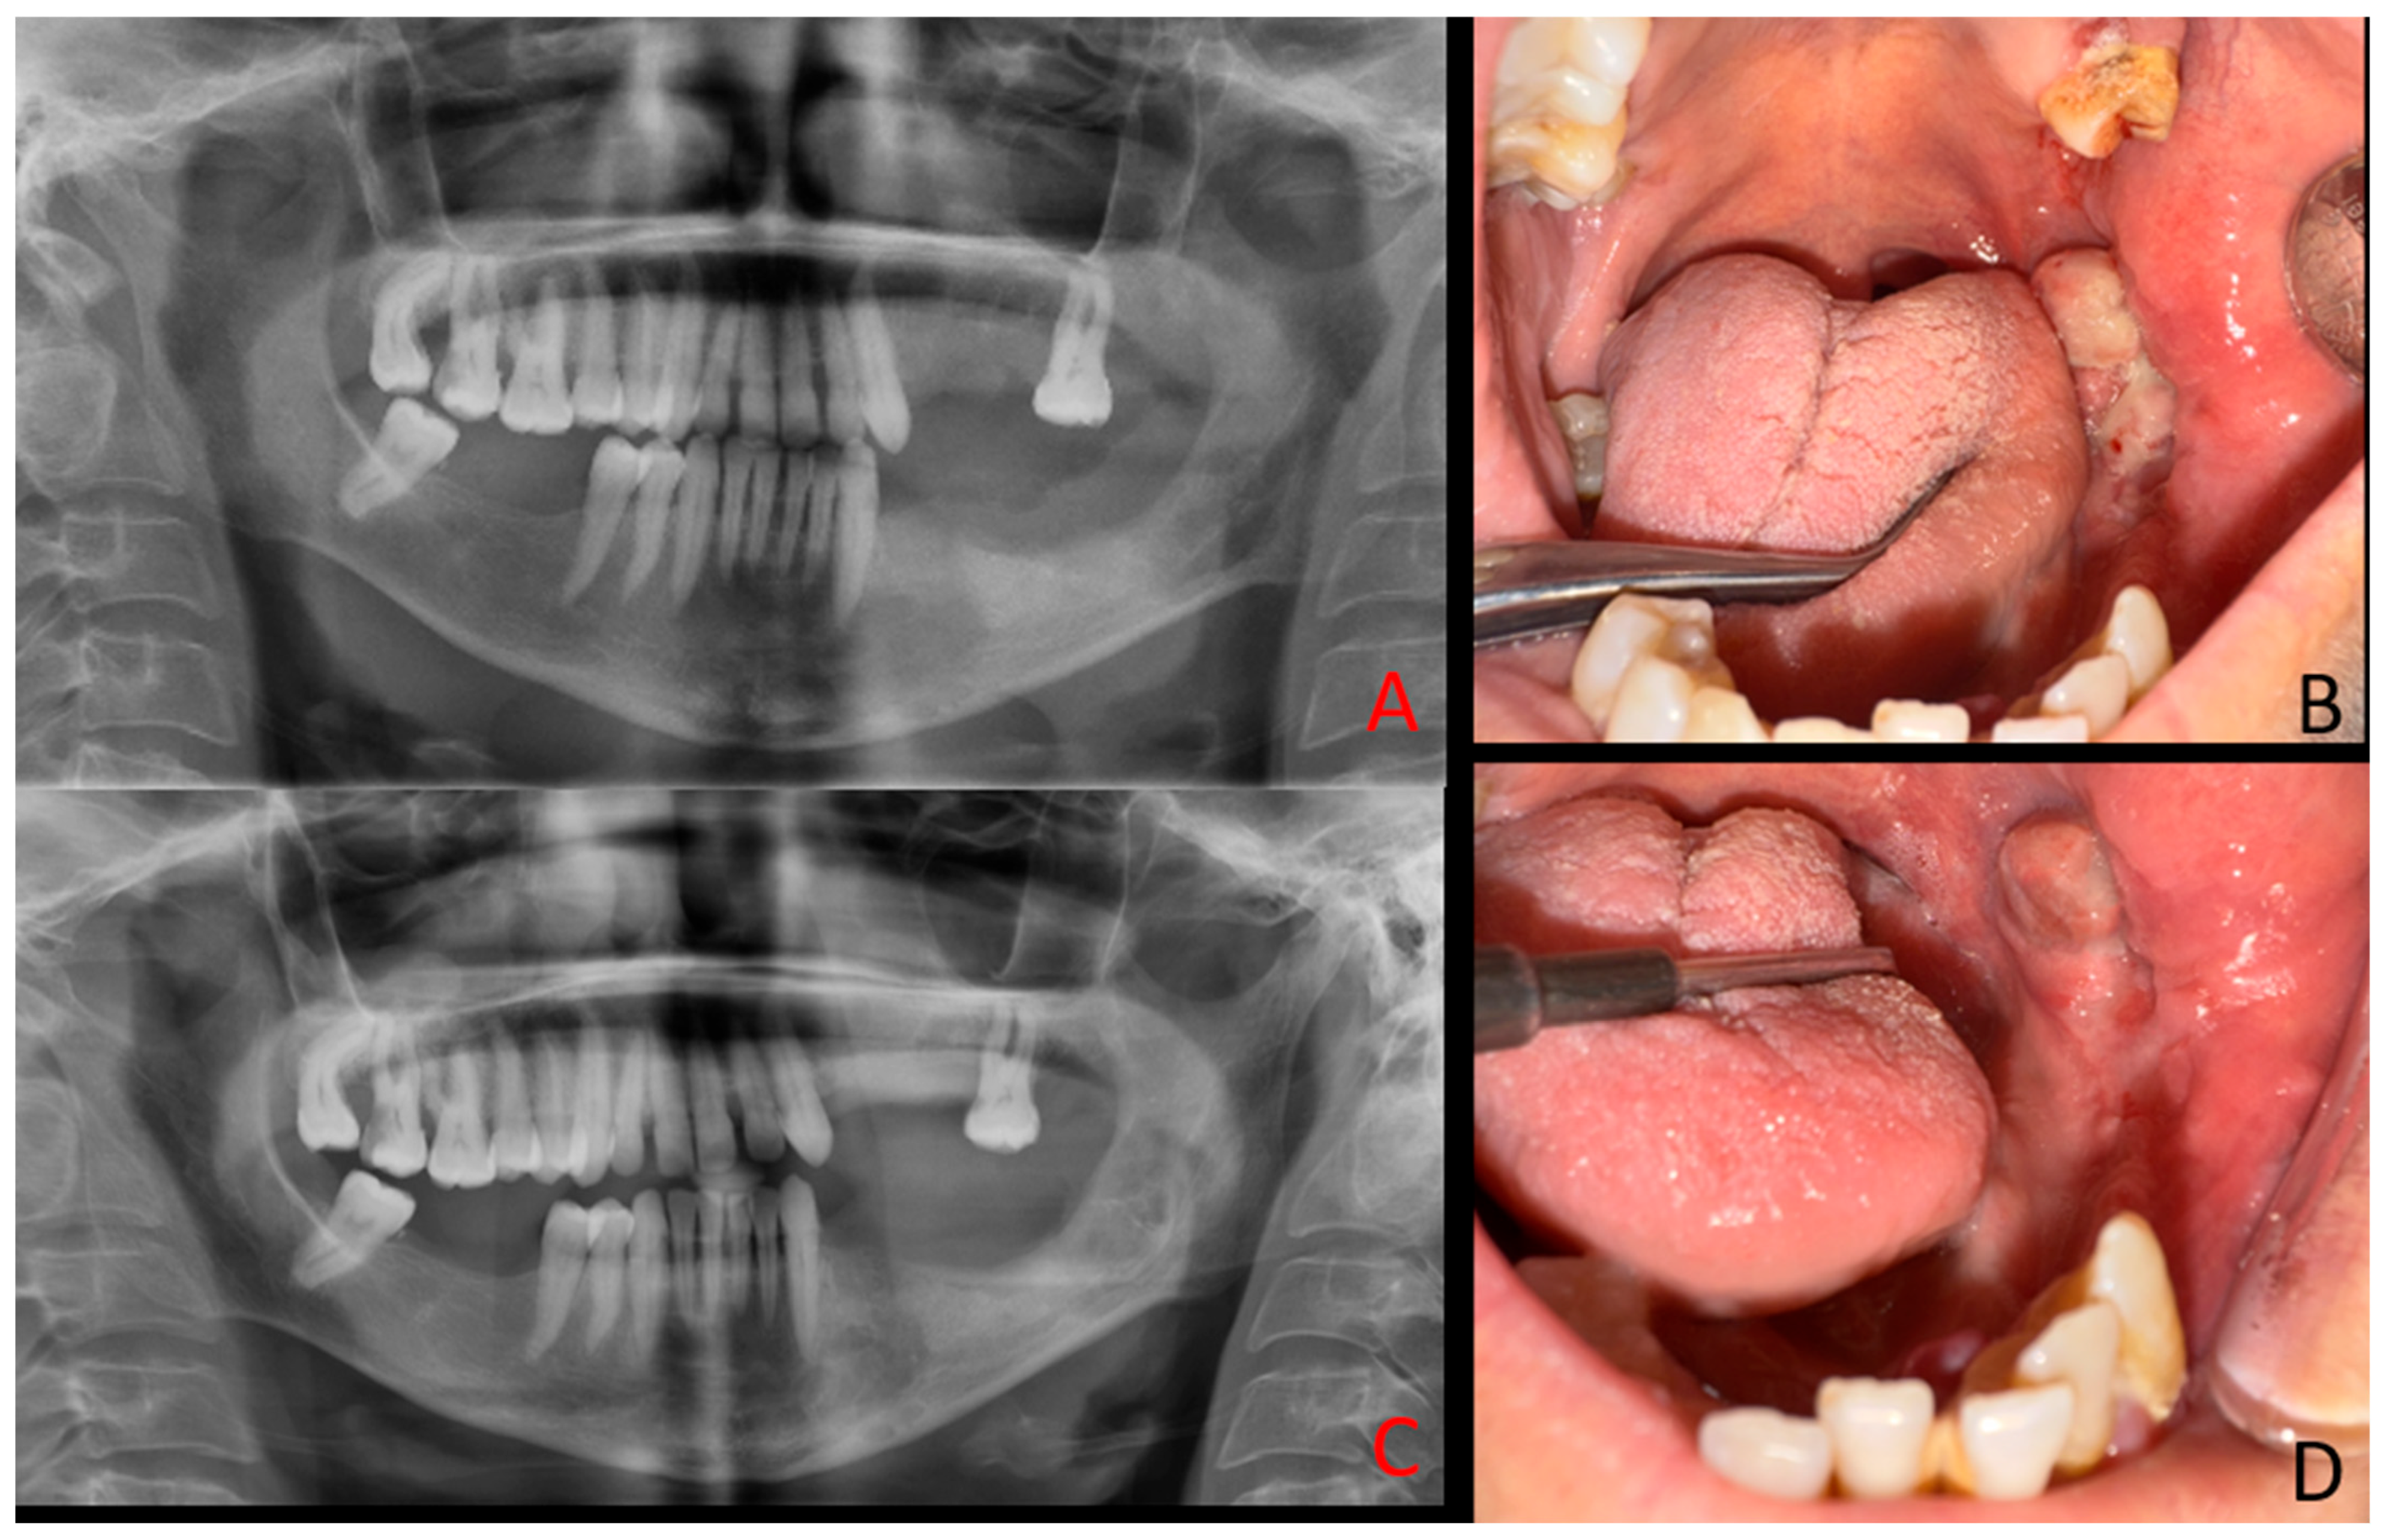

BTs are well-recognized skeletal manifestations of hyperparathyroidism, yet their occurrence in the mandible remains rare, particularly in the context of secondary hyperparathyroidism [7,8]. The present case is also distinctive for its unusual clinical course: unlike most BTs that regress following systemic management [9], the lesion demonstrated relentless progression and ultimately required complete surgical excision. Moreover, the clinical and radiological presentation closely mimicked aggressive odontogenic or malignant pathology. Clinically, the patient exhibited an exophytic, ulcerated mandibular mass with irregular borders and secondary infection, while radiologically, the multilocular osteolytic pattern with cortical perforation resembled ameloblastoma, central giant cell granuloma, primary intraosseous carcinoma, or osteosarcoma. This convergence of rarity, malignant-like presentation, and resistance to conventional endocrine therapy underscores the diagnostic and therapeutic dilemmas posed by mandibular BTs in secondary hyperparathyroidism. Sequential intraoral photographs and panoramic radiographs were obtained at 2 months and 4 months postoperatively. At 2 months, early signs of healing at the surgical site are evident (A,B). By 4 months, further bone remodeling and soft tissue recovery can be observed (C,D). The patient remains under regular medical and clinical follow-up to monitor changes in both intraoral and radiological appearance of the lesion. It should be noted that bone lesions accompanied by mucosal or gingival ulcerations, swelling, or erosions may mimic benign/malignant tumors rather than primary or secondary hyperparathyroidism, including central giant cell granuloma, ameloblastoma, and primary intraosseous squamous cell carcinoma. A mandibular lesion was initially diagnosed as a giant cell tumor before recognition as a Brown tumor [1], while another case presented with malignant-like features in the mandible [10]. Diagnostic confusion has also extended to lesions first interpreted as metastatic disease [11]. Radiological appearances such as multilocular “soap-bubble” or “moth-eaten” patterns, cortical perforation, and irregular borders are therefore not pathognomonic, underscoring the need for biochemical correlation with parathyroid hormone and alkaline phosphatase levels. Even with systemic control, persistence of aggressive jaw lesions has been reported after parathyroidectomy, necessitating surgical excision [12]. Further evidence confirms this overlap. Multiple destructive head-and-neck lesions were described in hyperparathyroidism, initially suggesting aggressive odontogenic disease [13]. Brown tumors of the mandible have repeatedly been mistaken for malignancies [10,14], while in other sites, lesions were treated as malignancies until endocrine testing revealed the true diagnosis [15]. More recently, histopathological resemblance to central giant cell granuloma has been documented in mandibular cases [16].